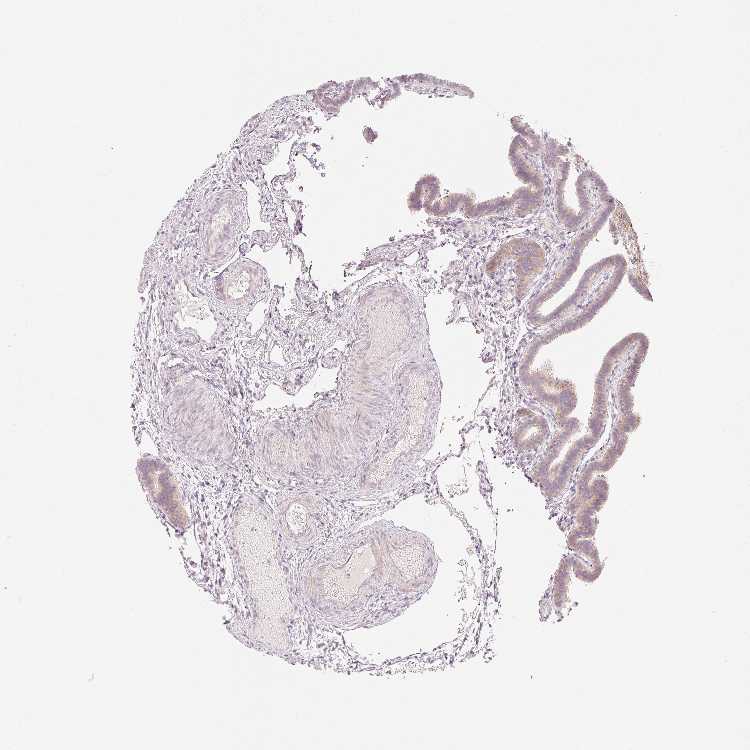

OR13C3